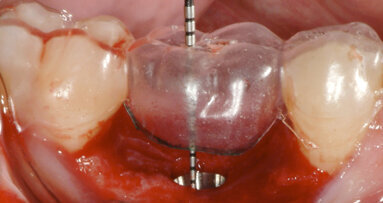

Prior to surgery, intra-oral scans of the edentulous upper jaw and dentate lower jaw were performed. The existing denture was used first as a surgical guide and then as a provisional prosthesis, after removing the palate (Fig. 4). Immediately after implant placement (Figs. 5–10), abutment position was registered with an intra-oral scan (Fig. 11). The provisional prosthesis was prepared fromthe existing denture (Figs. 12 & 13) and then the Atlantis BridgeBase was designed (Fig. 14).

Fig. 4: The existing denture was adapted to be used as a surgical guide and provisional prosthesis for immediate loading.